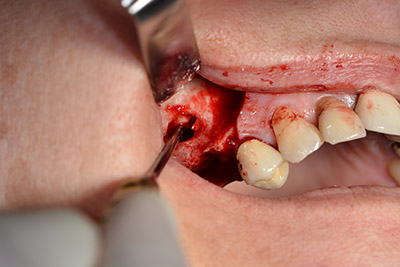

En el siguiente paso se efectúa la elevación del suelo del seno maxilar, a la vez que se coloca el implante. Para la fenestración lateral de la pared del seno maxilar Implantmed también cuenta con un ajuste predefinido en la primera posición.

La ventana se crea a una velocidad de 35.000 rpm y, a continuación, la membrana de Schneider se prepara en sentido craneal (figuras 13 a 14).

Acto seguido, se coloca el implante y se estructura el hueso. Dado el tamaño del aumento, en el caso que nos ocupa se utilizó hueso autógeno, que había surgido como virutas de fresado en el implante 16 y en la fenestración 14 y se había recogido con un colector óseo, y se combinó con material de reemplazo óseo.